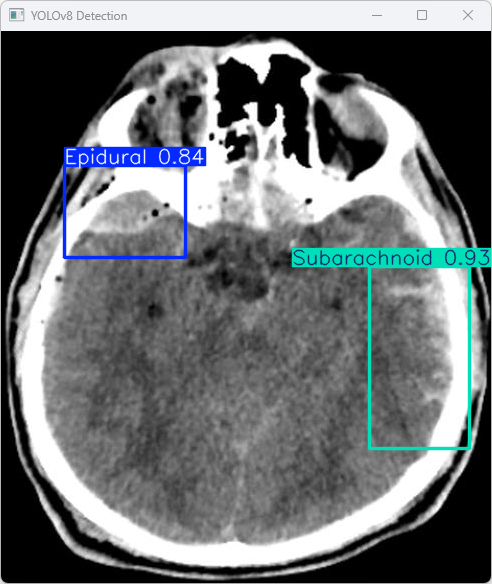

执行imgTest.py代码后,会将执行的结果直接标注在图片上,结果如下:

这段输出基于YOLOv8模型对图片"imagetest.jpg"进行了检测,并详细描述了具体结果。

图像信息:

(1)处理的图像路径为:TestFiles/imagetest.jpg。

(2)图像尺寸为640×576像素。

模型在图像中识别出:1个 Epidural(硬膜外)、1个 Subarachnoid(蛛网膜下腔)。

处理速度:

(1)预处理时间: 5.0 毫秒

(2)推理时间: 41.8 毫秒

(3)后处理时间: 64.9毫秒

YOLOv8模型通过成功完成对图像中两个类别的检测任务, 从而表明该模型在这些分类任务上的性能表现稳健.